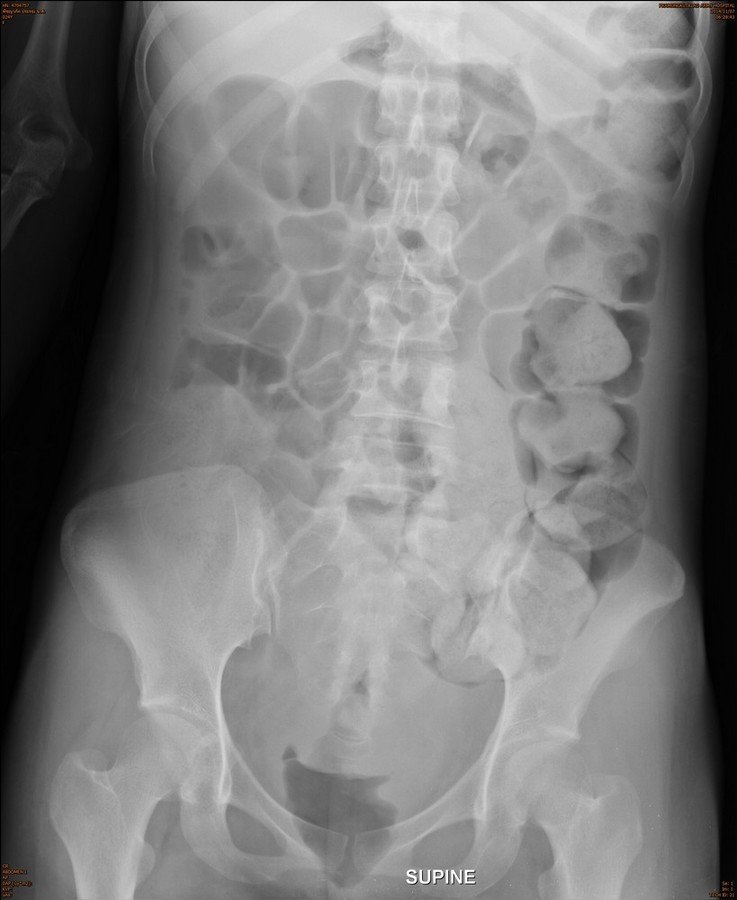

Additional plain film abdomen : upright

Air fluid levels with different height in the same loop of in dilated large bowel and small bowel.

Radiological finding :

• Colonic dilatation and fecal impaction at left side colon to the level of sigmoid colon

• Abrupt change of the colonic lumen at rectum

• Associated small bowel dilatation

Answer 1 : Large bowel obstruction

Answer 2 : Partial obstruction, because can see air in the rectum

Answer 3 : Site of obstruction : Rectum